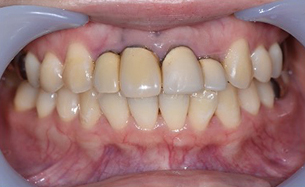

セラミッククラウン

の症例

| 主訴 | 前歯の形や大きさが気になる。 以前にかぶせ物を入れたが、 自分の顔に合っていない気がする。 |

| 年齢・性別 | 30代・女性 |

| 治療期間 | 2ヶ月 |

| 治療内容 | ジルコニアボンドクラウンを用いて、 強度も審美も最高のもので、 歯茎の高さも合わせて完成させる。 |

| 治療費用 | 5,500円(税込)×4 (プロビジョナルレストレーション(仮歯)×4本) 歯ぐきの手術 55,000円(税込) |

| 治療方針 | 左右の歯のバランスを同じ数値で シンメトリーとする。 |

| 特記事項 | 回数かかっても良いので、 キレイに美しく仕上げて欲しい。 |